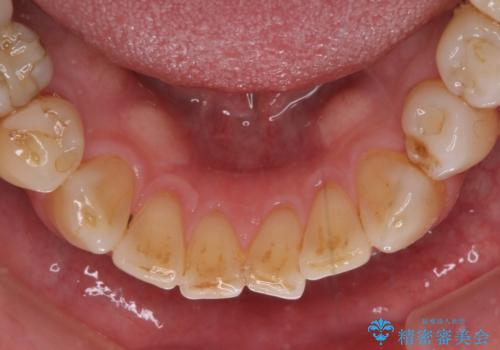

憧れの白い歯に 全顎セラミック治療

- 60歳を越え、黄ばんだ前歯をセラミッククラウンできれいな口元にしたいとのことで来院された患者様です。

診察したところ、前歯は反対咬合であり、その影響で抜歯が必要な奥歯があることが分かりました。

抜歯が必要な奥歯は、インプラント並びにブリッジにより補綴を行い、上下前歯は反対咬合を改善させるように補綴治療を行うこととしました。

健全な歯を削ってセラミッククラウンに置き換えることは、本来避けるべき治療と考えますが、今回は①患者様が60歳を越えていること、②要改善の咬合により抜歯が必要な奥歯があること、③反対咬合の前歯改善の手段としてセラミック治療が選択肢にあることなどから、全顎的なセラミック治療を行うこととしました。